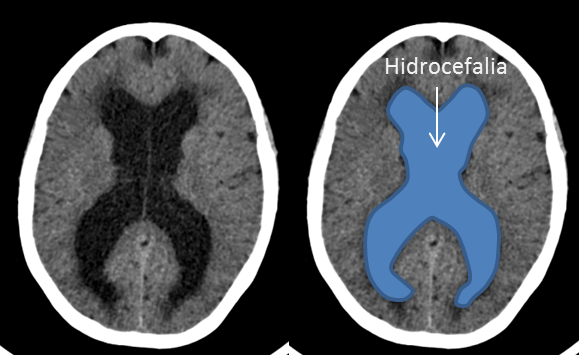

Se trata de un paciente de 63 años que comienza de forma subaguda con torpeza a la marcha y urgencia e incontinencia miccional. Acudió al servicio de urgencias donde se le realizó una TAC cerebral sin contraste (imagen 1 y 2) donde se observaba una hidrocefalia y se derivó a estudio ambulatorio con la sospecha de hidrocefalia normotensiva (imagen 2). La hidrocefalia se produce como consecuencia del aumento del líquido cefalorraquideo en el sistema ventricular cerebral o el espacio subaracnoideo.

La presentación clínica de un quiste coloide del III ventrículo puede ser la misma que la de una hidrocefalia a presión normal (alteración de la marcha, incontinencia urinaria y alteración cognitiva). Los quistes coloides del III ventrículo se suelen ver en la TAC cerebral sin contraste porque en 2/3 de las ocasiones son hiperdensos pero en 1/3 de los casos como éste caso son isodensos/hipodensos y pueden pasar desapercibidos inicialmente. Además hay que tener en cuenta que cuando se introduce contraste en la TAC cerebral puede no verse tampoco. Únicamente tras la realización de la resonancia cerebral se pudo diagnosticar por su hiperintensidad en secuencias T1 (imagen 3) y su hipointensidad en secuencias en T2.